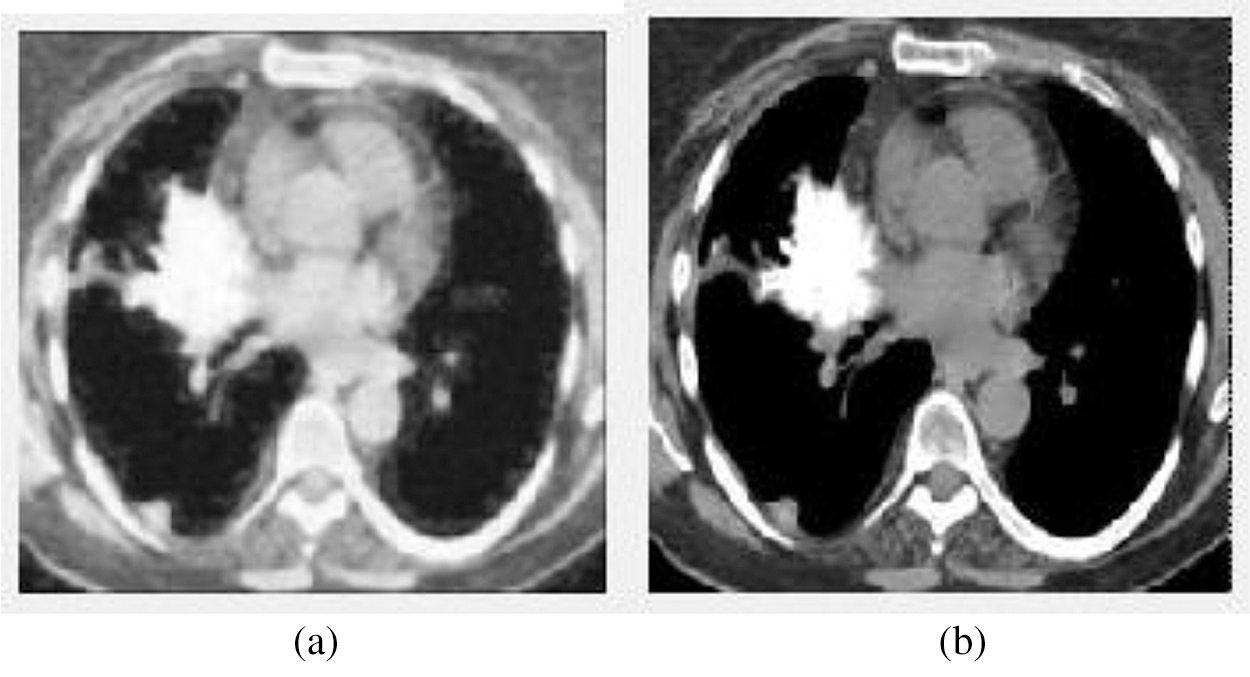

Figure 3: The input and output of the image preprocessing stage. (a) The input image (b) The preprocessed output image

We can see from the above Fig. 3, Fig. 3a shows the input image, and Fig. 3b displays the preprocessed image using the Adaptive Median Filter. The preprocessed image is enhanced the image quality and is fed to the next stage—the segmentation process.